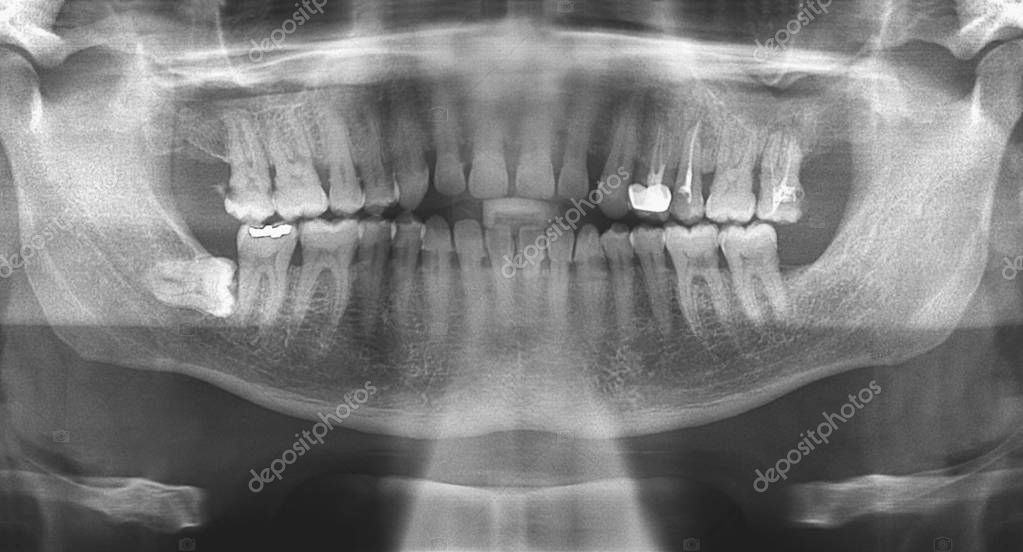

From depositphotos.com

Dental panoramic radiograph — Stock Photo © alfonsodetomas 139707980 Dental Panoramic Anatomy Anatomy and structures, as well as various technique errors and how to correct them. Upon completion of this course, the. Panoramic imaging (also called pantomography) is a technique for producing a single image of the facial structures that includes both the maxillary and the mandibular dental arches and their supporting structures (fig. This technique produces a tomographic image in that. Dental Panoramic Anatomy.